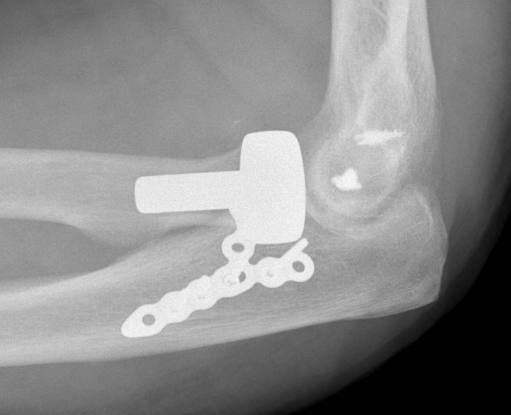

Medial approach and buttress plate with LCL repair